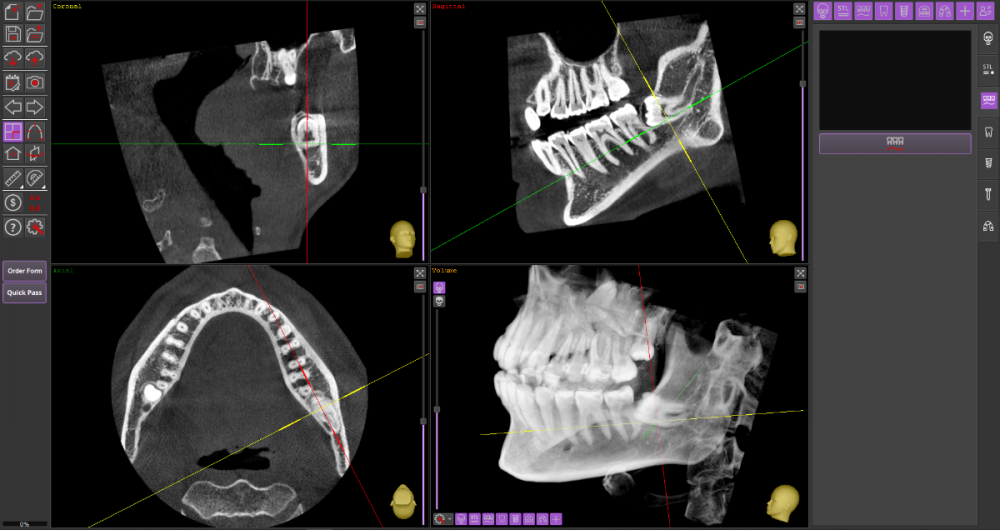

Прошу Вашего совета по поводу удаления восьмых зубов.

Из жалоб есть непродолжительная ноющая боль в правой нижней челюсти, не связанная с внешними раздражителями.

1. Необходимо ли удаление зубов мудрости?

2. Возможно ли удаление амбулаторно, без общего наркоза?

3. Нет ли риска для семёрок при удалении.

Виновником боли в н.ч. справа может быть, например зуб 46, не только 48.

1. Удаление 8-х зубов скорее всего необходимо

2. Удаление амбулаторно вполне возможно. Общая анестезия (наркоз) совершенно необязательна, местной анестезии достаточно.

3. Несчастные случаи бывают, но крайне редко.